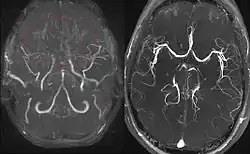

Links die MR-Angiographie eines 11-jährigen Mädchens mit Moyamoya. Das typische, wolkige Gespinst anstelle der normalen vorderen und mittleren Hirnarterien ist markiert. Rechts MRA eines Gesunden zum Vergleich.

Als Moyamoya-Erkrankung (von jap. moyamoya „nebelig“) bezeichnet man eine Krankheit der Gehirngefäße, bei der es zu einer Verengung oder einem Verschluss von beidseitigen Hirn-Arterien kommt, im Regelfall der Arteria carotis interna und der Arteria cerebri media, und bei der sich dadurch eine relative Blutarmut (Schlaganfall und transitorische ischämische Attacke) im Gehirn einstellt. Es bilden sich viele kleine kompensatorische Gefäße als Umgehungskreisläufe aus, die diese Minderdurchblutung kompensieren sollen, andererseits auch so fragil sind, dass sie platzen und zu Hirnblutungen führen können.

Der Name der Erkrankung leitet sich von der Tatsache ab, dass die vielen dünnen Gefäße in der Angiografie wie ein Nebelgebilde aussehen.